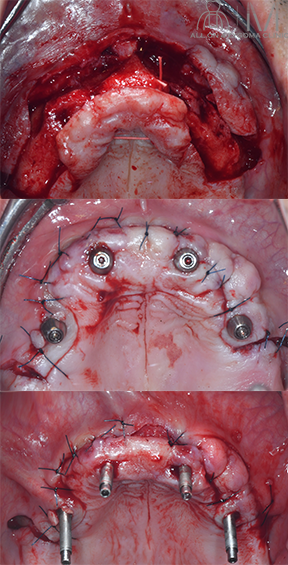

手術所見

術式:静脈内鎮静法下、上下顎All-on-4

(多数歯抜歯術、ザイゴマインプラント埋入術)施行

手術時間:3時間23分

術後口腔内所見